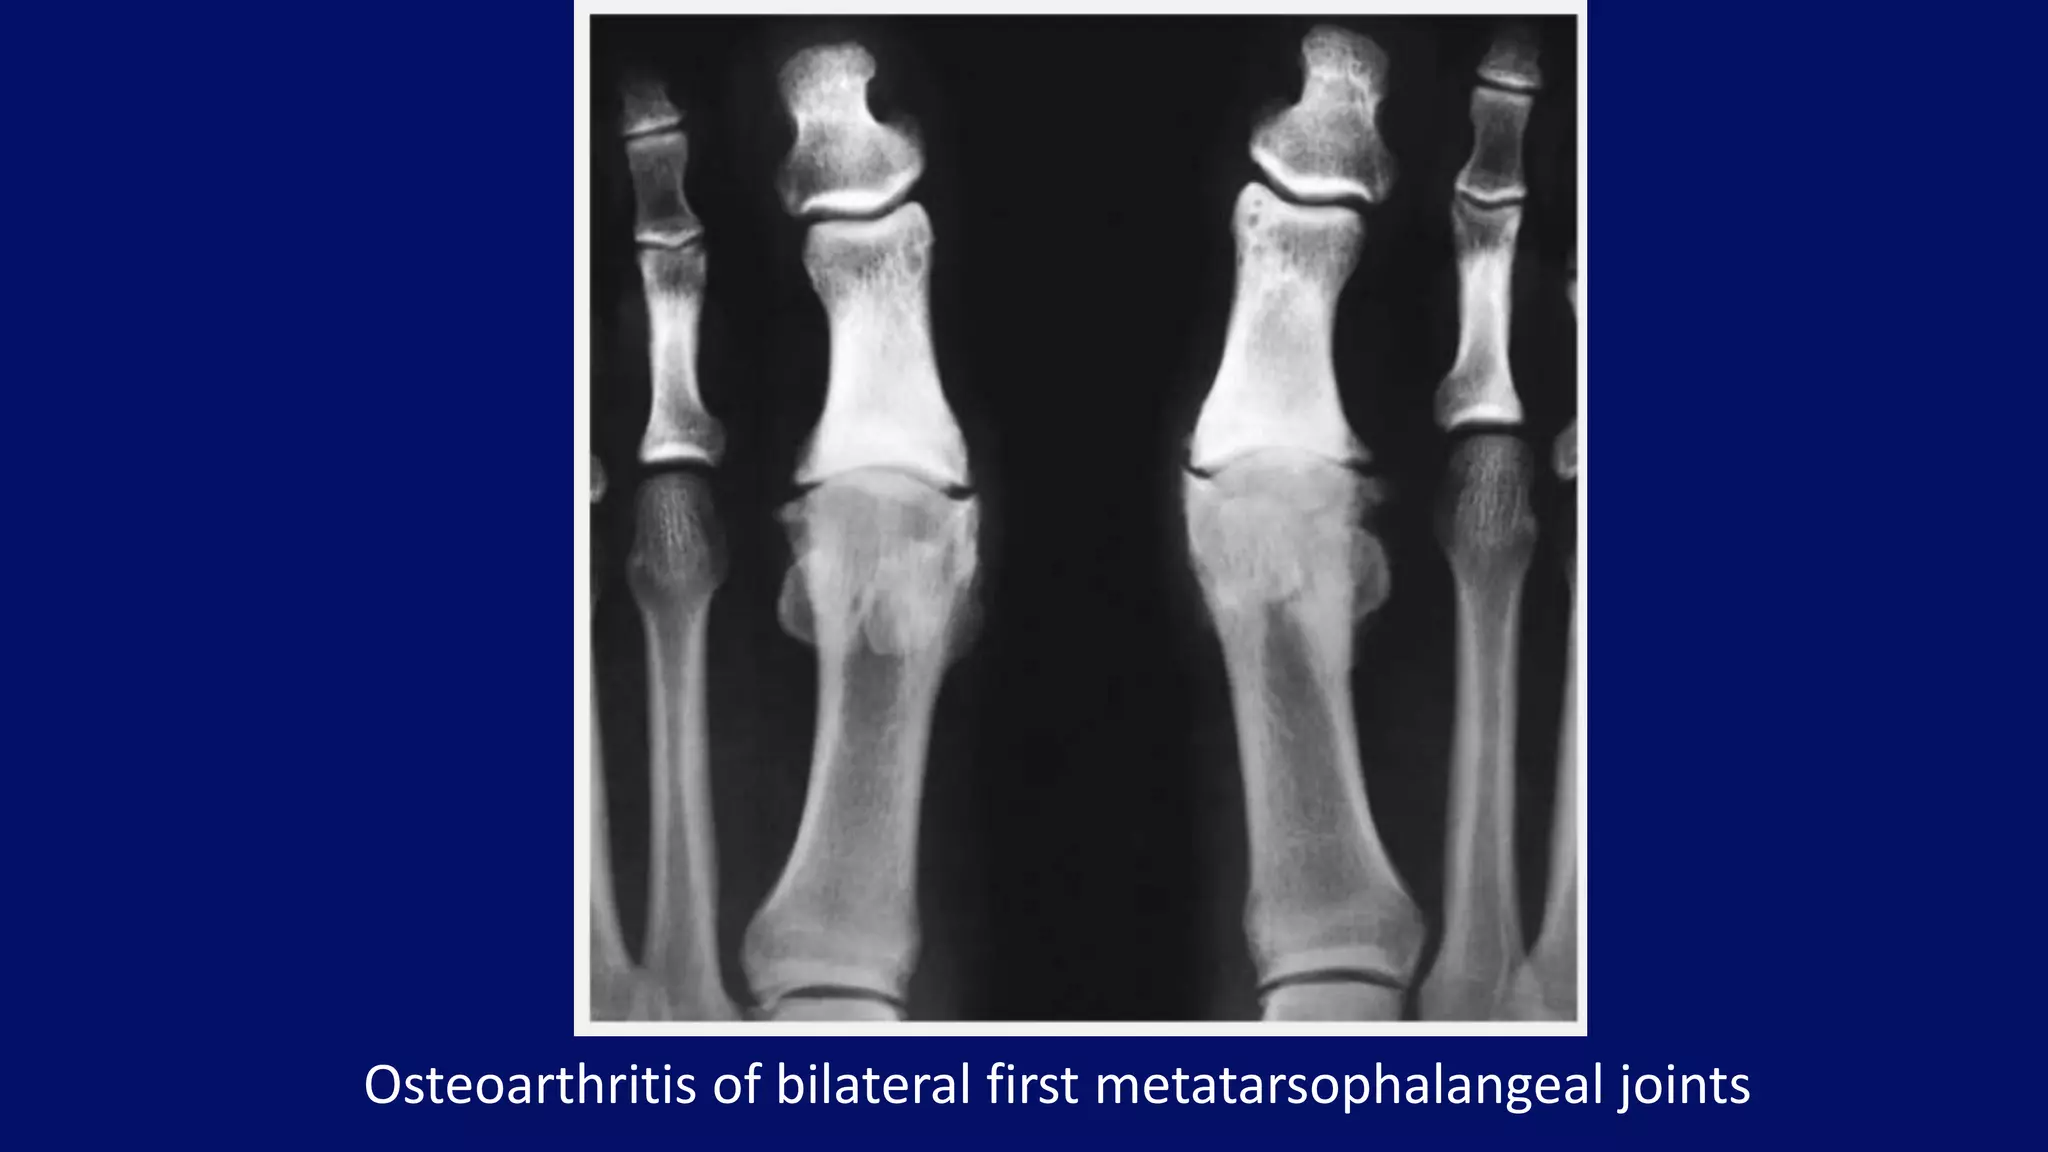

Osteoarthritis of bilateral first metatarsophalangeal joints

• #35 Dorsoplantar radiograph of the great and second toes of the feet of a 33-year-old man shows osteoarthritis of the first metatarsophalangeal joints, which are known as hallux rigidus (hallux limitus). Note the narrowing of the joint space, subchondral sclerosis, and marginal osteophytes. Degenerative arthritis and stiffness due to bone spurs that affects the MTP joint at the base of the hallux (big toe) is called hallux rigidus or stiff big toe.